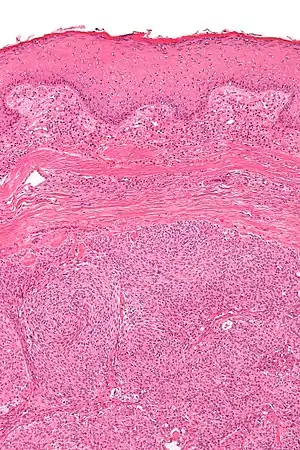

Micrograph showing an acrospiroma. H&E stain.

Hidradenoma refers to a benign adnexal tumor of the apical sweat gland.[1][2] These are 1–3 cm translucent blue cystic nodules. It usually presents as a single, small skin-colored lesion, and may be considered closely related to or a variant of poromas.[3] Hidradenomas are often sub-classified based on subtle histologic differences, for example:[4]